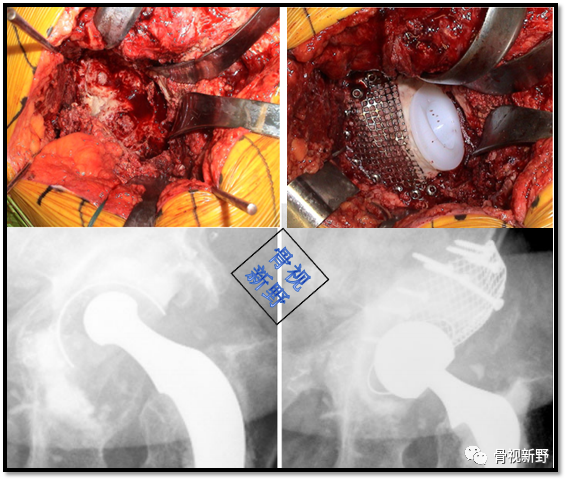

Case 1: Paprosky IIIb

男性,78岁。因右髋部骨折,于25年前行右髋THA。入院前半年开始出现右髋部疼痛、活动受限,加重1月。影像资料提示假体松动、移位;股骨侧及髋臼侧严重骨缺损(Paprosky IIIb )。

完善术前常规检查后,择期行翻修术:髋臼侧以cup-in-cup技术翻修;股骨侧以水泥柄翻修。

术后X光片